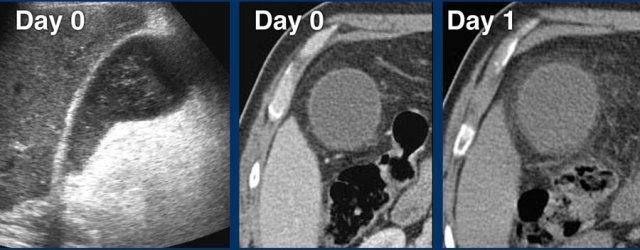

Vào ngày 0, có phù nề túi mật cấp tính do sỏi bị kẹt.

Một ngày sau, bệnh nhân không còn triệu chứng.

Sỏi vẫn còn tại chỗ, nhưng rõ ràng cho phép mật lưu thông qua ống túi mật, vì phù nề đã biến mất.

Phù nề tái tưới máu và bùn mật là những dấu hiệu chứng nhân thầm lặng của cơn đau trước đó.

CRP vẫn bình thường.